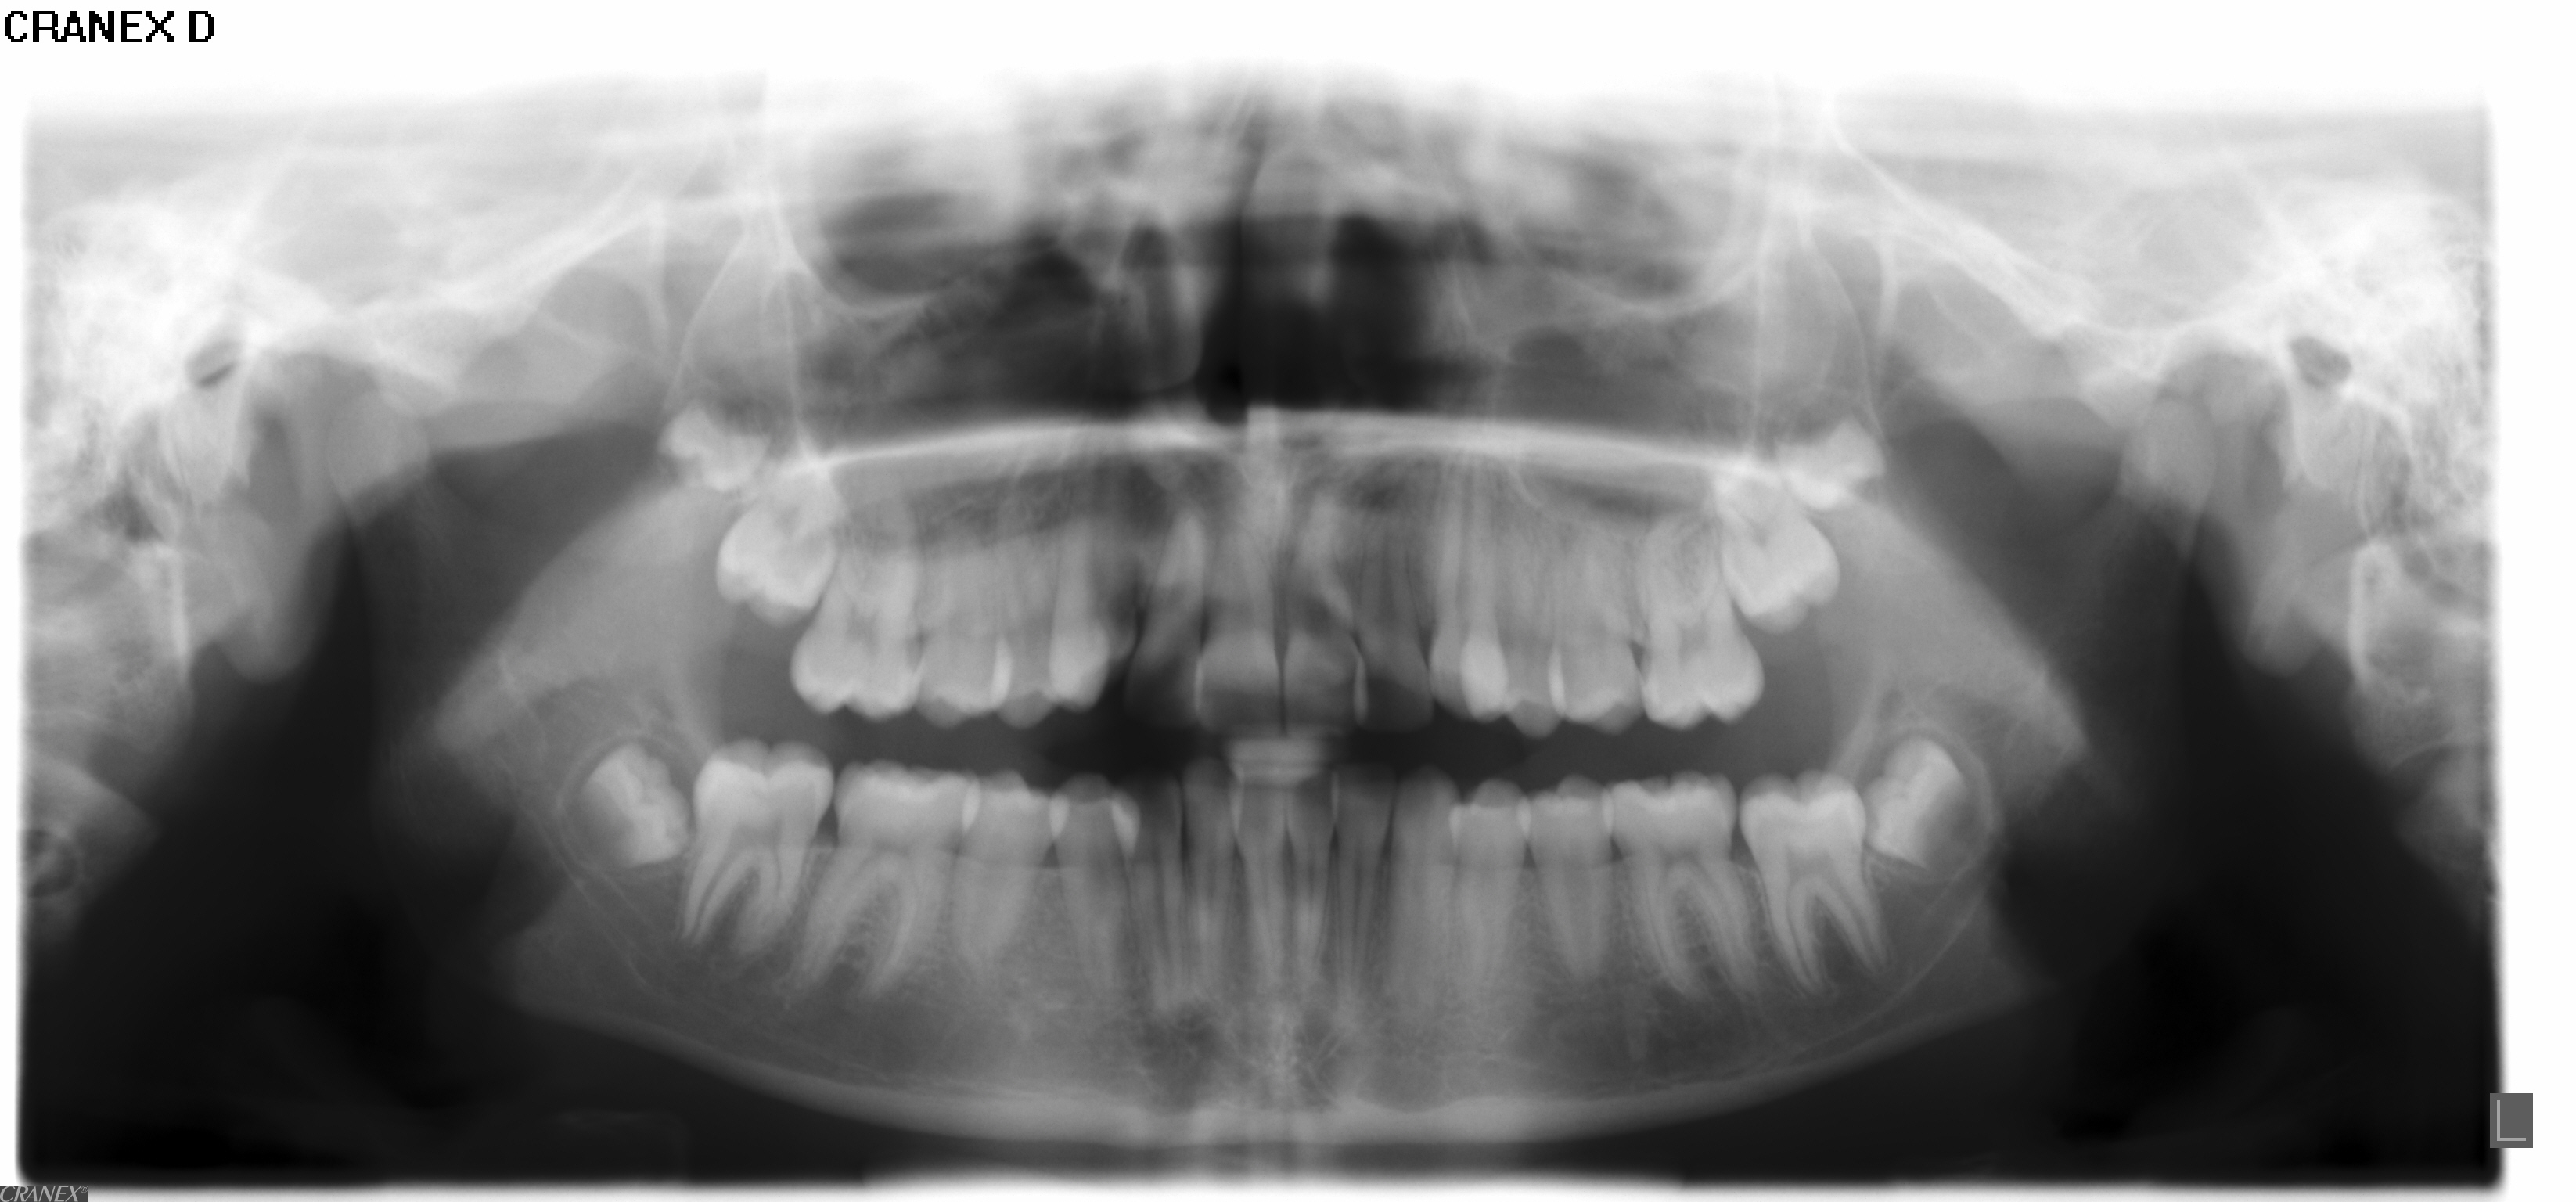

Der bliver taget billeder "udenpå og indeni" samt røntgenbilleder.

• Panorama viser, om alle tænder er anlagt, og om tandrødder og kæbeled ser normale ud.

• Profilrøntgen giver et billede af, hvordan kæberne er placeret i forhold til hinanden og i forhold til resten af kraniet. Derudover giver det et indtryk af, hvordan væksten vil udfolde sig.

• I nogle tilfælde tages der også et røntgenbillede af hånden, for at se hvor langt dit barn er i sin vækst.

• Der tages røntgenbillede af fortænderne i overkæben som et referencebillede, da disse af og til bliver skadet lidt af en bøjlebehandling. Cirka et halvt år inde i behandlingen bliver der taget ét billede igen som kontrol.

• Alt materiale studeres af en specialtandlæge, der udarbejder en behandlingsplan.